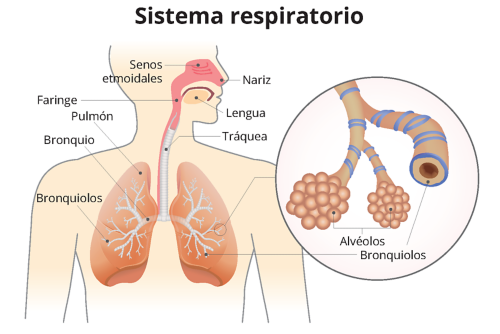

consecuencias

problemas respiratorios

daña las celulas del sistema respiratorios

carviovasculares

disminucion de oxigeno